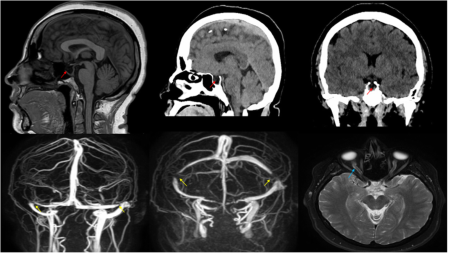

Report of the Month: Idiopathic intracranial hypertension presenting with isolated unilateral facial nerve palsy

Idiopathic intracranial hypertension is a disorder characterized by increased intracranial pressure of unclear pathogenesis in the absence of other structural and obstructive lesions. It should be suspected in obese young women presenting with headache and transient visual complaints and some cranial nerve abnormalities. This report aims to draw attention to the possibility of idiopathic intracranial hypertension presenting with unilateral cranial nerve VII palsy as the only cranial nerve involved, which needs a high index of suspicion by clinicians. (Samara et al., 2019)